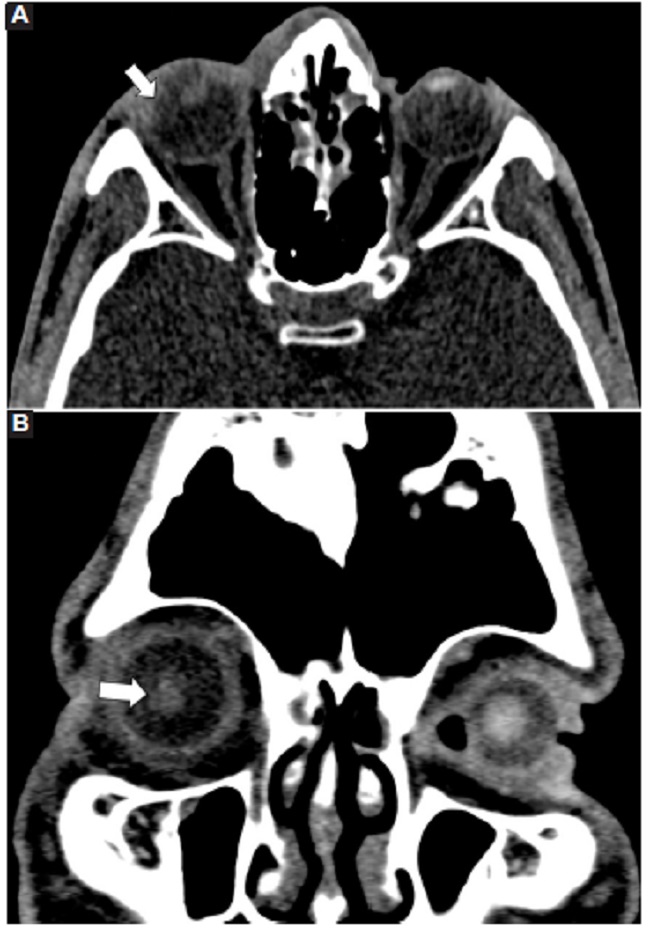

Las calcificaciones oculares y el material médico se pueden confundir con cuerpos extraños u otras lesiones orbitarias1. Las localizaciones típicas de las calcificaciones permiten diferenciarlas de cuerpos extraños hiperdensos. Las más frecuentes son las calcificaciones trocleares, las placas esclerales, las drusas del nervio óptico y la ptisis bulbi. Las primeras tienen localización superomedial dentro de la órbita (Fig. 13), en la tróclea del músculo oblicuo superior, aunque se pueden observar en todas las edades, hay mayor prevalencia de calcificaciones trocleares en pacientes con enfermedades autoinmunes y niveles elevados de fosfatasas alcalinas. Las placas esclerales se localizan en los sitios de inserción de los músculos rectos medial y lateral (Fig. 14) y son más comunes en los pacientes ancianos. Las calcificaciones que ocurren cerca del disco óptico se conocen como drusas del nervio óptico (Fig. 15), las cuales se asocian a degeneración macular y pueden ser causa de pseudopapiledema benigno. La ptisis bulbi es una atrofia y calcificación del globo ocular como secuela de enfermedades infecciosas, inflamatorias o traumáticas previas (Fig. 16) (1,11. Los imitadores de lesiones abiertas del globo ocular incluyen las deformidades como coloboma, estafiloma y el globo ocular elongado por glaucoma o miopía (Fig. 17). Las masas orbitarias y los hematomas también pueden alterar el contorno del globo ocular y asociarse a calcificaciones o relacionarse con desprendimiento de retina (Fig. 18) (1,6,8,11.

Los cambios postratamiento y los dispositivos orbitarios también pueden malinterpretarse como patologías traumáticas. Dentro de estos cambios se incluyen la faquectomía con reemplazo del cristalino, las hebillas esclerales (Figs. 19 y 20), las inyecciones intraoculares de aceite de silicona, la retinopexia neumática y las prótesis de globo ocular1,6,11. Para diferenciar la silicona intraocular de hemorragia se ha propuesto la medición de las UH, siendo la atenuación > 100 UH sugerente de silicona y < 90 UH de sangre11 (Fig. 20).